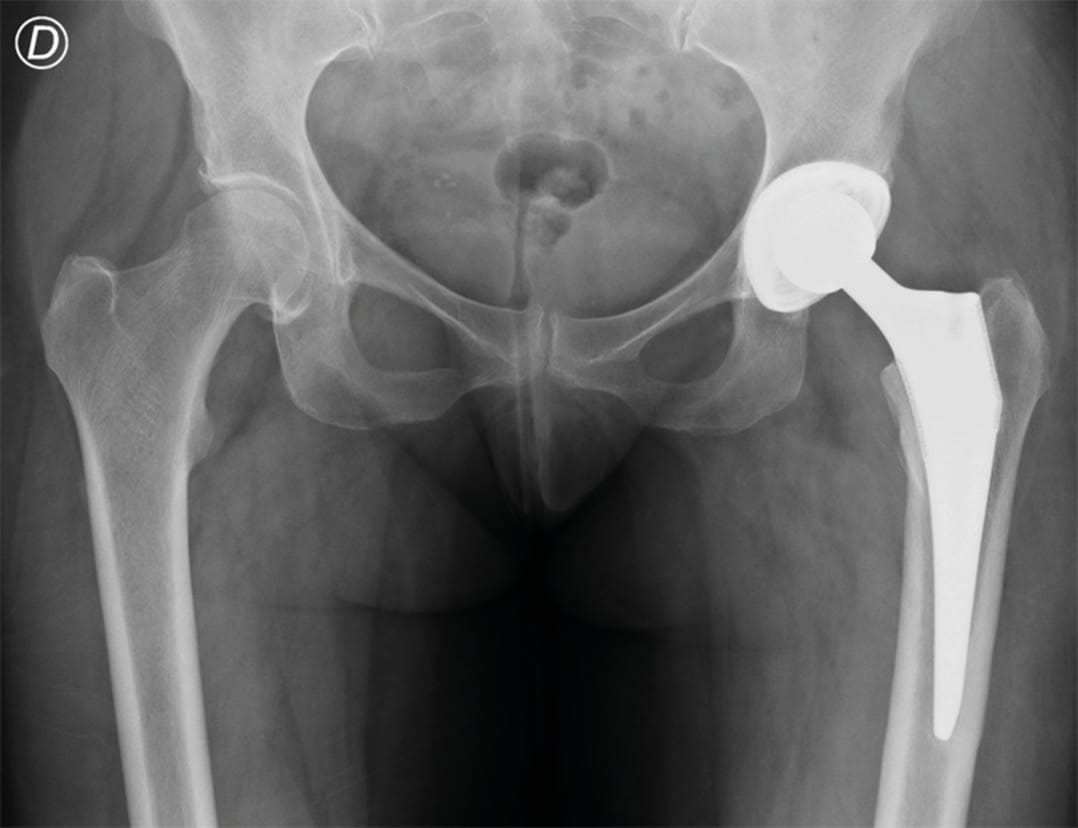

A 58-year-old woman consulted at our department with a history of high blood pressure, dyslipidemia and primary uncemented left total hip arthroplasty for osteoarthritis 9 months before, with a satisfactory result and a Harris Hip Score of 92 points. She presented walking without assistance complaining of right hip pain of 2 months duration. She referred dull pain, with an intensity of 5 on the visual analog scale and having received a steroid injection in the painful hip 6 weeks after the onset of symptoms and 15 days before consultation. Physical examination showed moderate pain during motion, with hip flexion 10 to 100°, internal rotation of 15° and external rotation of 20°. There was no fever or erythema in the area. At that time, an X-ray of both hips was performed which showed a normal right hip and left THA (Figure 1).